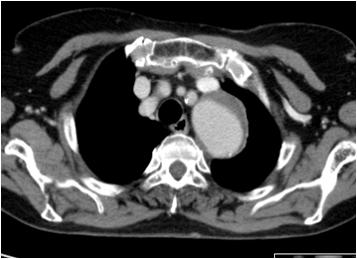

Dilatação Aneurismática da Aorta Torácica